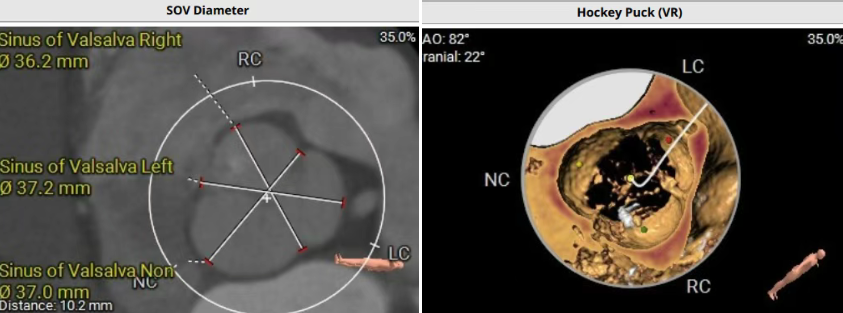

术前CT评估提示,患者主动脉瓣三叶瓣,瓣叶增厚,舒张期右冠瓣脱垂,右冠瓣瓣叶轻度钙化,存在三个瓣窦,分布较均匀;主动脉瓣环周长折算直径28.0mm;左心室流出道周长折算直径29.5mm,无钙化,无狭窄;STJ直径35.3mm,升主动脉直径41.8mm;双侧冠脉开口高度可LCA13.5mm ,瓣叶长17.2mm;RCA33.9mm,瓣叶长10.0mm;侧左冠脉轻度钙化;横位心,左室主动脉夹角为135°;